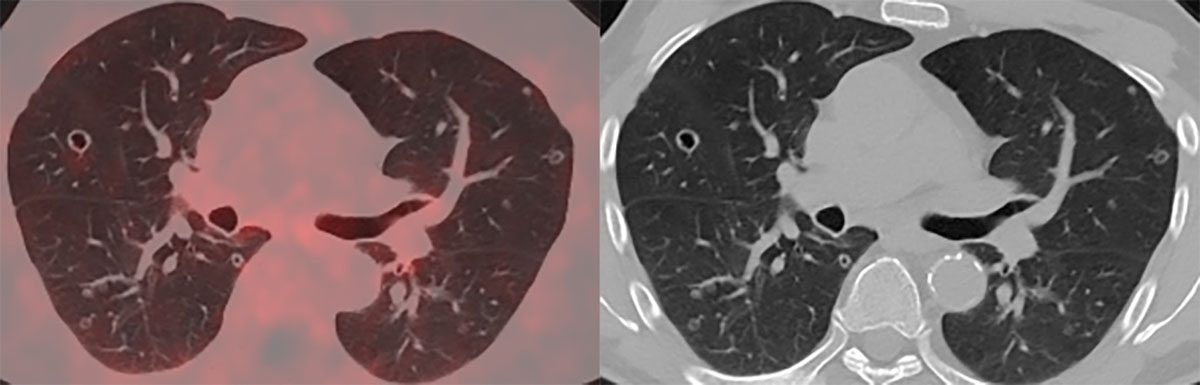

In November 2020, PSA-levels increased to 6 ng/mL and a third follow-up F18-PSMA-PET-CT revealed multiple, thin- and thick-walled, excavated, pericentrimetric, randomly distributed, nodular lung lesions with a slightly metabolic avid wall bilaterally (Figure 1) and enlarged para-iliac lymph nodes. The lymph nodes were treated with three sessions of stereotactic body radiation therapy in January 2021. The lung nodules were not treated, as their metastatic potential was considered low based on their morphology. A fourth F18-PSMA-PET-CT in May 2021 (Figure 2) and a CT-thorax in June 2021 (Figure 3) showed PSMA-uptake and increased volume and number of the cavitary lung nodules. A broad differential diagnosis of vasculitis, granulomatous disease, infectious/septic embolisms and atypical metastases was suggested.

Figure 2